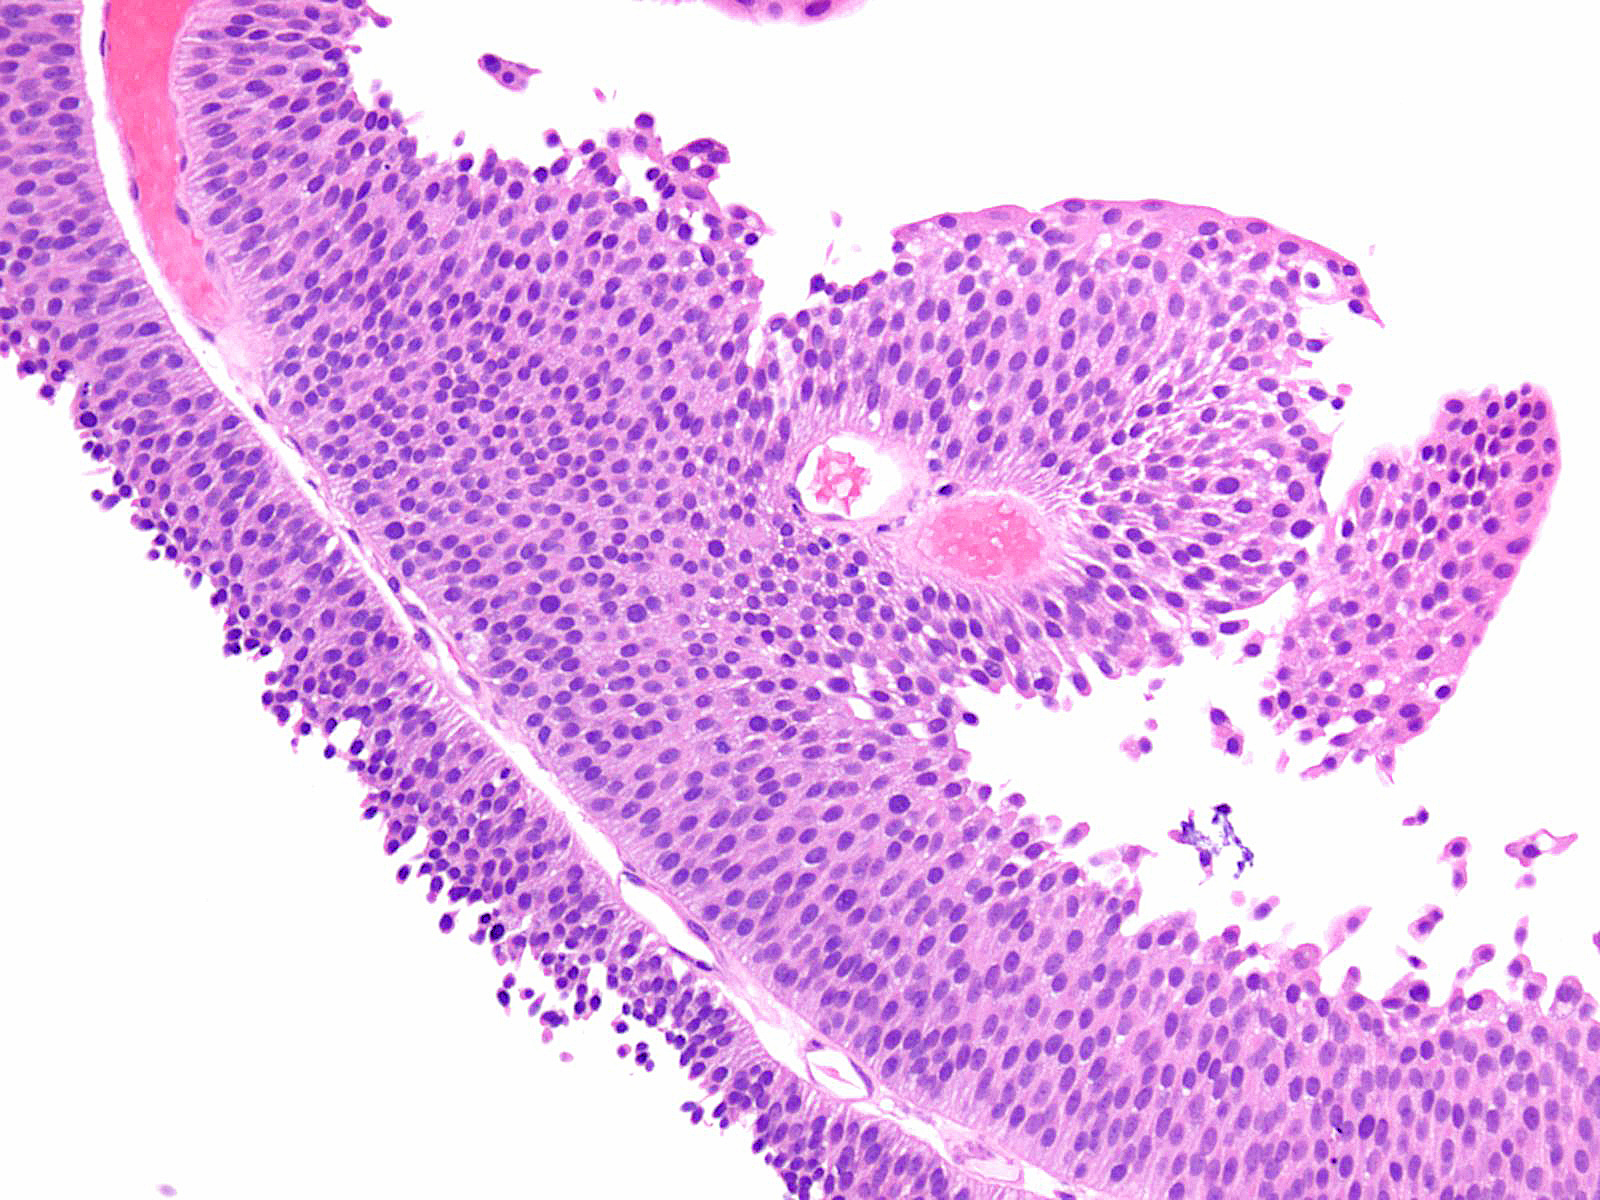

Bladder Papillary Lesions

Case ID: 149